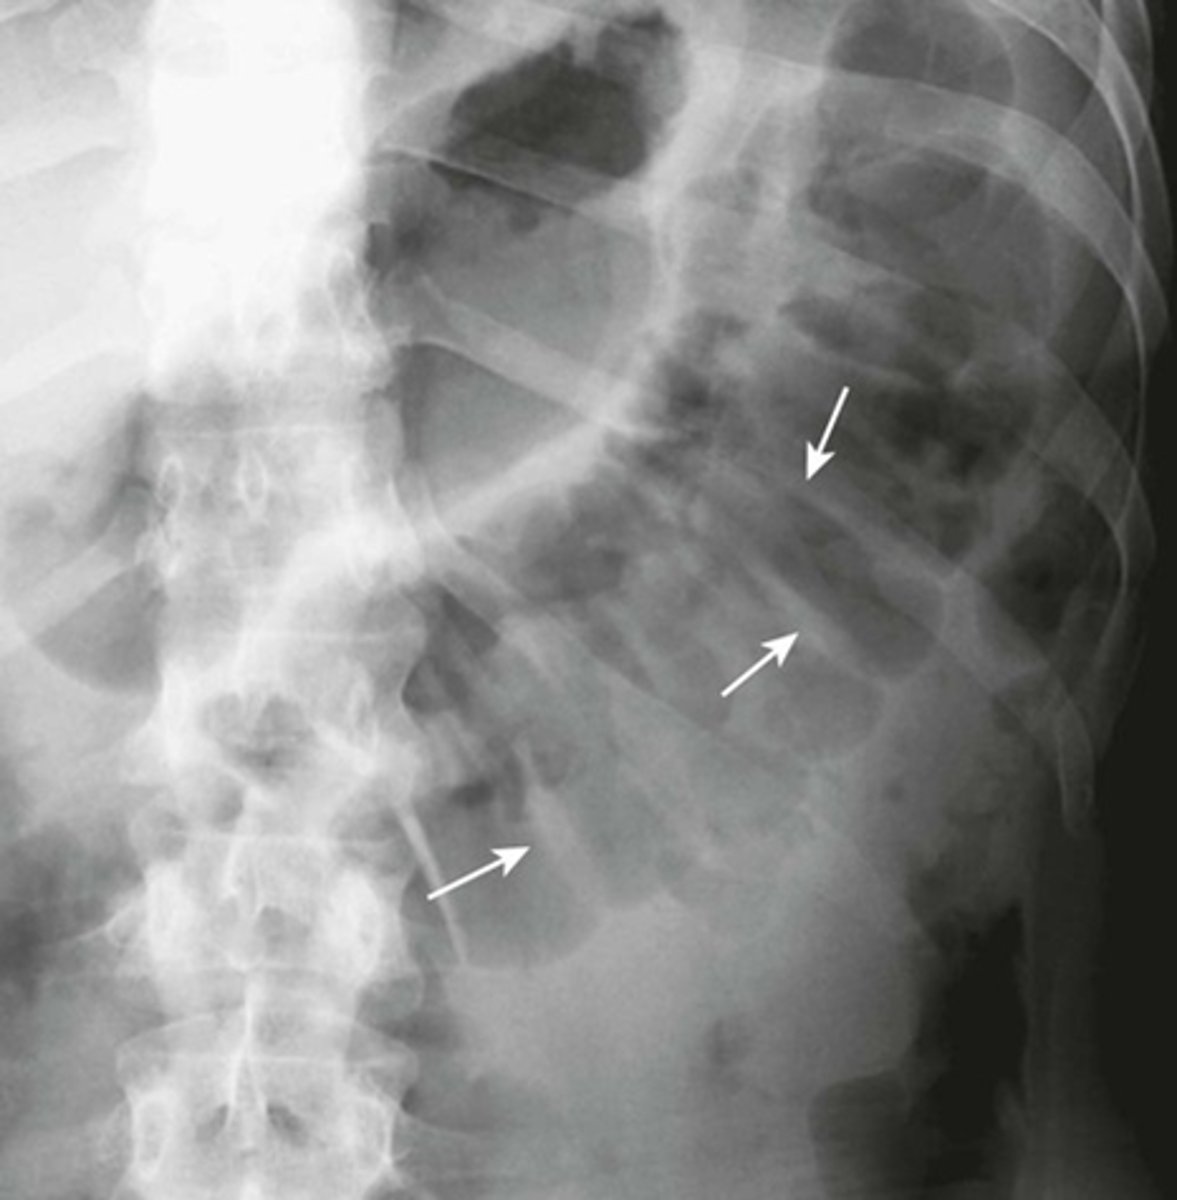

Pneumatosis cystoides intestinalis.

SOLID WHITE ARROWS:

Clusters of air-containing CYSTs associated with the left colon.

Portal air in liver secondary to pneumatosis